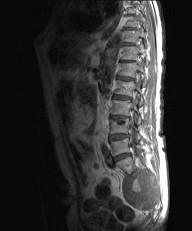

常见的椎管内肿瘤(如图所示)有()A.脊膜瘤B.胶质瘤C.血管瘤D.上皮样囊肿E.神经鞘瘤

问题 常见的椎管内肿瘤(如图所示)有()

选项 A.脊膜瘤 B.胶质瘤 C.血管瘤 D.上皮样囊肿 E.神经鞘瘤

答案 ABCDE